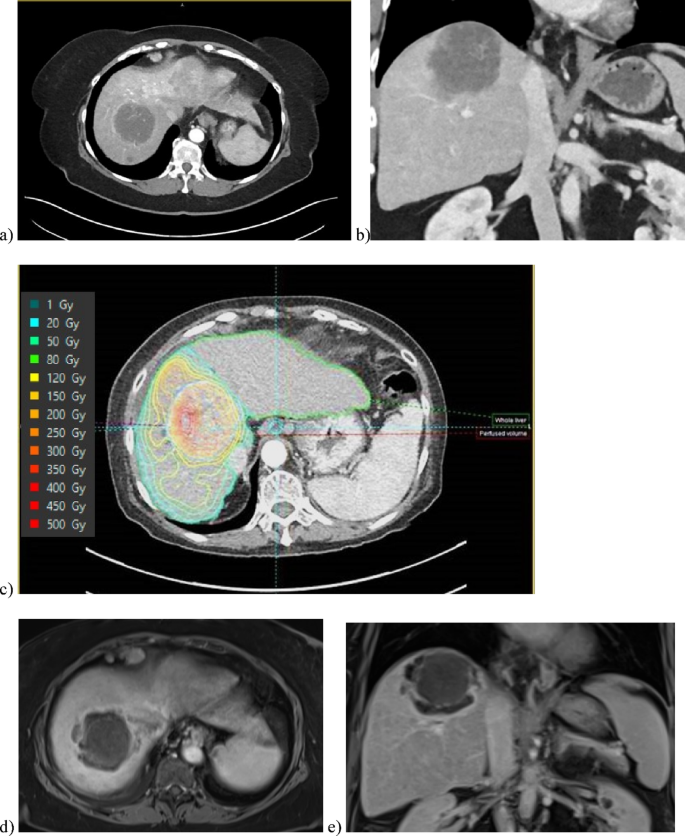

Institutional review board approved this retrospective study of patients who underwent radioembolization with 90Y glass microspheres (Boston Scientific Corporation, Marlborough, MA). The final cohort was derived from patients identified with hypovascular tumors after reviewing all 90Y-RE treatments at a single institution between January 2022 and December 2023. For inclusion criteria, hypovascularity of the tumors was defined as the presence of tumoral enhancement less than background liver enhancement during the arterial phase of contrast on MRI or CT, followed by gradual enhancement or no enhancement during the portal venous and delayed phases relative to the normal liver (Fig. 1a, b). Exclusion criteria included tumors with pre-existing necrosis. Tumor hypovascularity was confirmed by 3 board-certified radiologists with 18, 13, and 8 years of experience, respectively. Patients were excluded if they did not undergo MAA SPECT/CT imaging, or the imaging did not include uptake surrounding the index lesion. All methods were carried out in accordance with relevant guidelines and regulations, and are in accordance with the Declaration of Helsinki.

Pre-treatment CT axial (a) and coronal (b) of a 66 year-old female with pathology-proven poorly differentiated carcinoma favoring intra-hepatic cholangiocarcinoma (ICC) measuring 5.6 cm x 5.2 cm. Arterial-phase CT demonstrates decreased enhancement compared to background liver. (c) Reconstruction software demonstrates iso-lines of Tc99m-MAA uptake overlaid on pre-treatment contrast-enhanced CT of the tumor. Axial (d) and coronal (e) MR scan of tumor demonstrating complete response and central necrosis 29 days following treatment.

Patients were followed with triphasic computed tomography (CT) or magnetic resonance imaging (MRI) at 1-month post-procedure and then at 3-month intervals after radioembolization (Fig. 1d,e). Index tumor response to treatment, evaluated using mRECIST criteria, was classified as complete response (CR), partial response (PR), stable disease (SD), or progressive disease (PD)10. Despite tumors being hypoenhancing to background liver on arterial phase of contrast, there was still some degree of enhancement on either arterial or delayed phase imaging, and thus non-enhancing tissue on post-procedure imaging could still be defined separately from untreated hypovascular tumor. Digital subtraction sequences on MR and CT were also used to arbitrage difficult cases. Treatment response with the use of mRECIST criteria was determined by a board-certified radiologist with 9 years of experience.